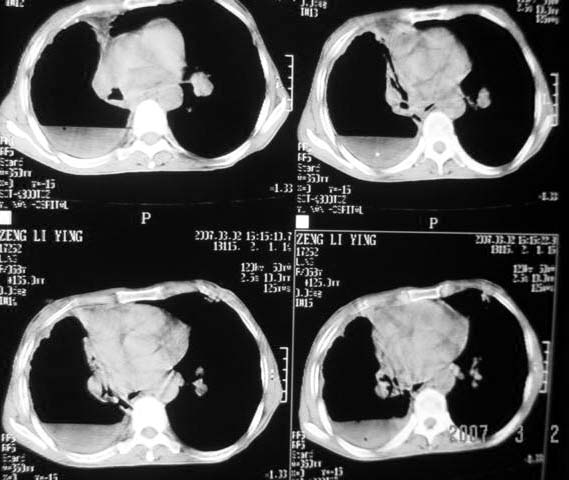

以下是引用dyqct在2007-3-2 22:04:00的发言:[br]考虑:1、右侧毁损肺伴支气管胸膜瘘(多条支气管与胸腔相通、液气胸);[br] 2、左肺浸润型肺结核。[br][br][br][br]